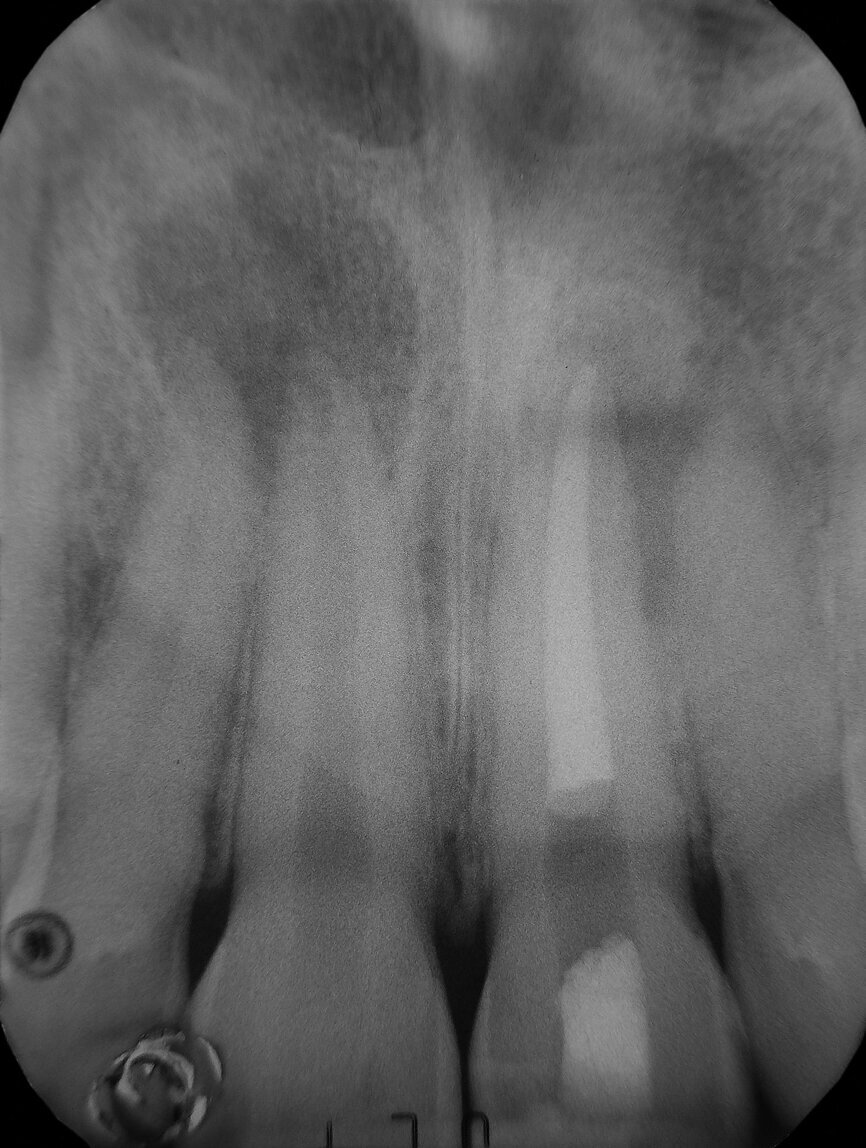

Post-operative radiograph (Image: Dr Vittorio Franco, UK and Italy)

The 22-year-old male patient had a history of trauma to his maxillary incisors and arrived at my practice with symptoms related to tooth #21. The tooth, opened in an emergency by the patient’s mother, was tender when prodded, with a moderate level of sensitivity on the respective buccal gingiva. Sensitivity tests were negative for the other central incisor (tooth #12 was positive), and a periapical radiograph showed radiolucency in the periapical areas of both of the central incisors. The apices of these teeth were quite wide and the length of teeth appeared to exceed 25 mm.

I suctioned the sodium hypochlorite, checked the working length with a paper point and then obturated the canal with a of 3 mm in thickness plug of bioactive cement. I then took a radiograph before obturating the rest of the canal with warm gutta-percha. I used a compomer as a temporary filling material.

The symptoms resolved, so I conducted the second treatment only after some months, when the tooth #11 became tender. Tooth #21 had healed. I performed the same procedure and obtained the same outcome (the four-month follow-up radiograph showed healing).